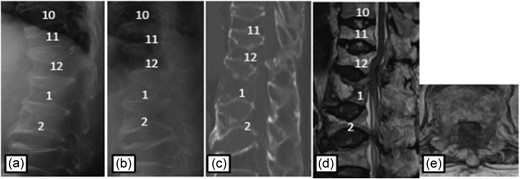

Plain radiographs on initial assessment (a) and on admission (b); Sagittal CT image (c) showing the hyperextension fracture at L1 and dislocation of it; MRI T2-weighted image (d, e) showing the severely compressed spinal cord at L1 level.